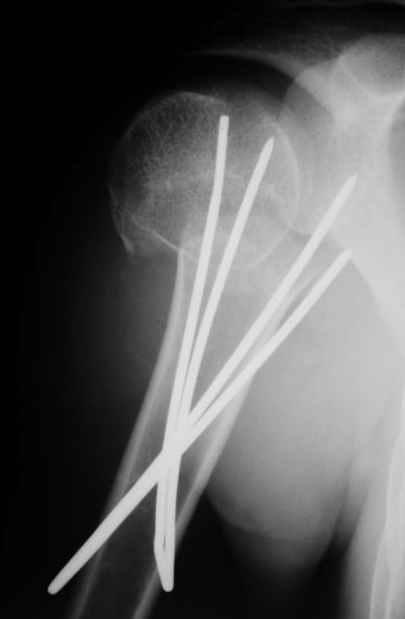

Пока я пользуюсь методикой принятой у нас (методика Сиэтла), также перкутанный спицевой метод, только сцицы 2.8 мм с резбой на конце.

Здесь случай перелома-вывиха плеча, больному 56 лет, после "дважды" закрытой неудачной репозиции, опять же ургентно взяли в операционную, после полного общего обезболивания попытались сделать репозицию, и фиксацию провели спицами.

Больной находился в повязке, примерно напоминяющей косыночную, рекомендованы движения в локтевом суставе и маятниковые движения в плече, спицы удалены в три недели (были случаи миграции)

Больной амбулаторный, предупрежден на случай осложнения АВН головки.